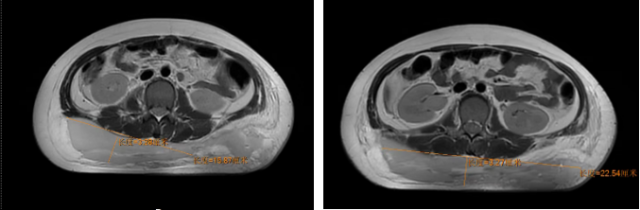

术前患儿影像,可见大面积血肿

术前患儿影像,可见盆骨骨折